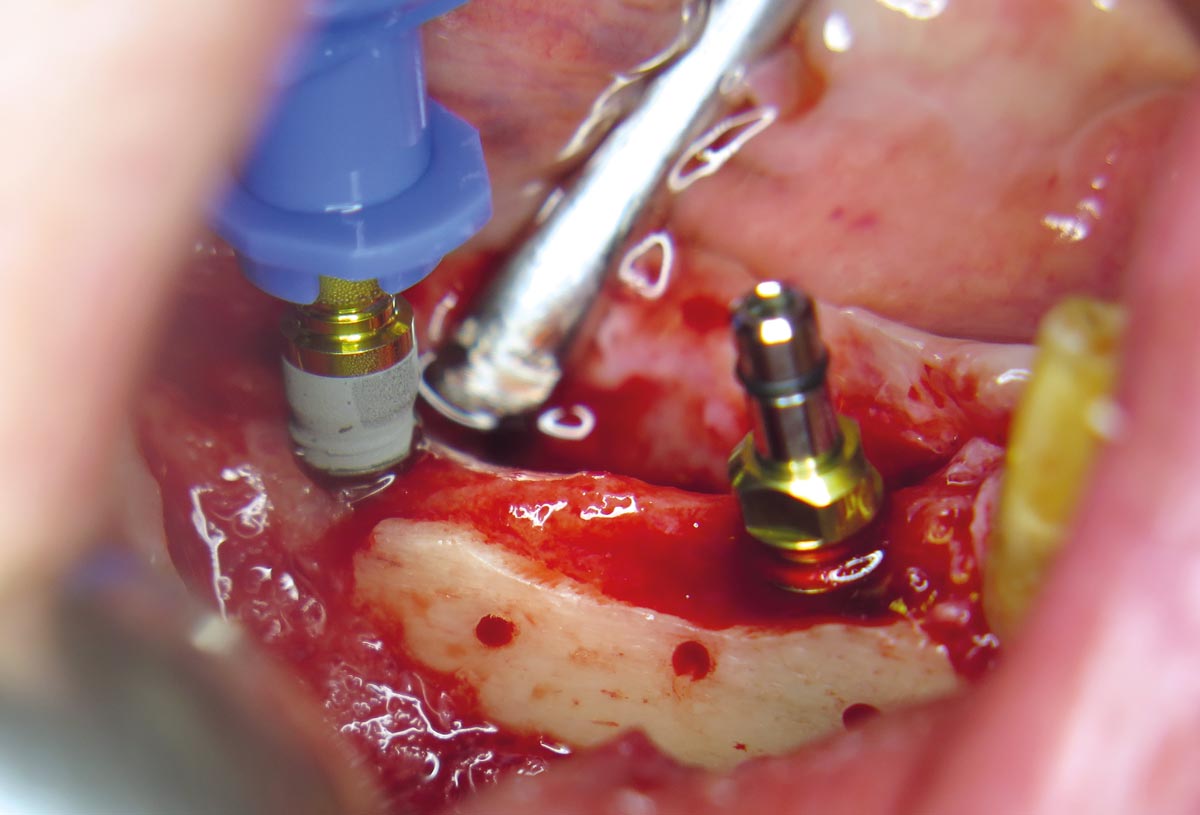

10 / 20 - Placing of pilot drills into the new formed bone tissueHorizontal ridge augmentation with maxgraft® cortico - M.Sc. E. Kapogianni

11 / 20 - Insertion of two dental implants in regio 44 and 46Horizontal ridge augmentation with maxgraft® cortico - M.Sc. E. Kapogianni

12 / 20 - Stable and fully submerged positioning of implantsHorizontal ridge augmentation with maxgraft® cortico - M.Sc. E. Kapogianni